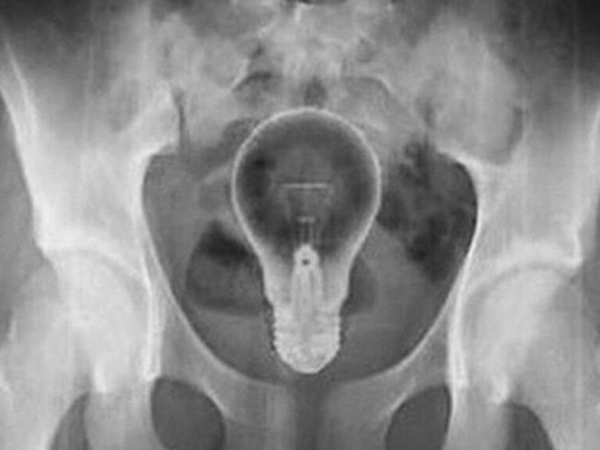

Lâmpada foi retirada do ânus de homem de 53 anos | Foto: Reprodução-Twitter

Ele chegou ao hospital com fortes dores e relatou aos médicos que não sabia do que se tratava. No entanto, exames de raio-X mostraram o objeto dentro do seu reto.